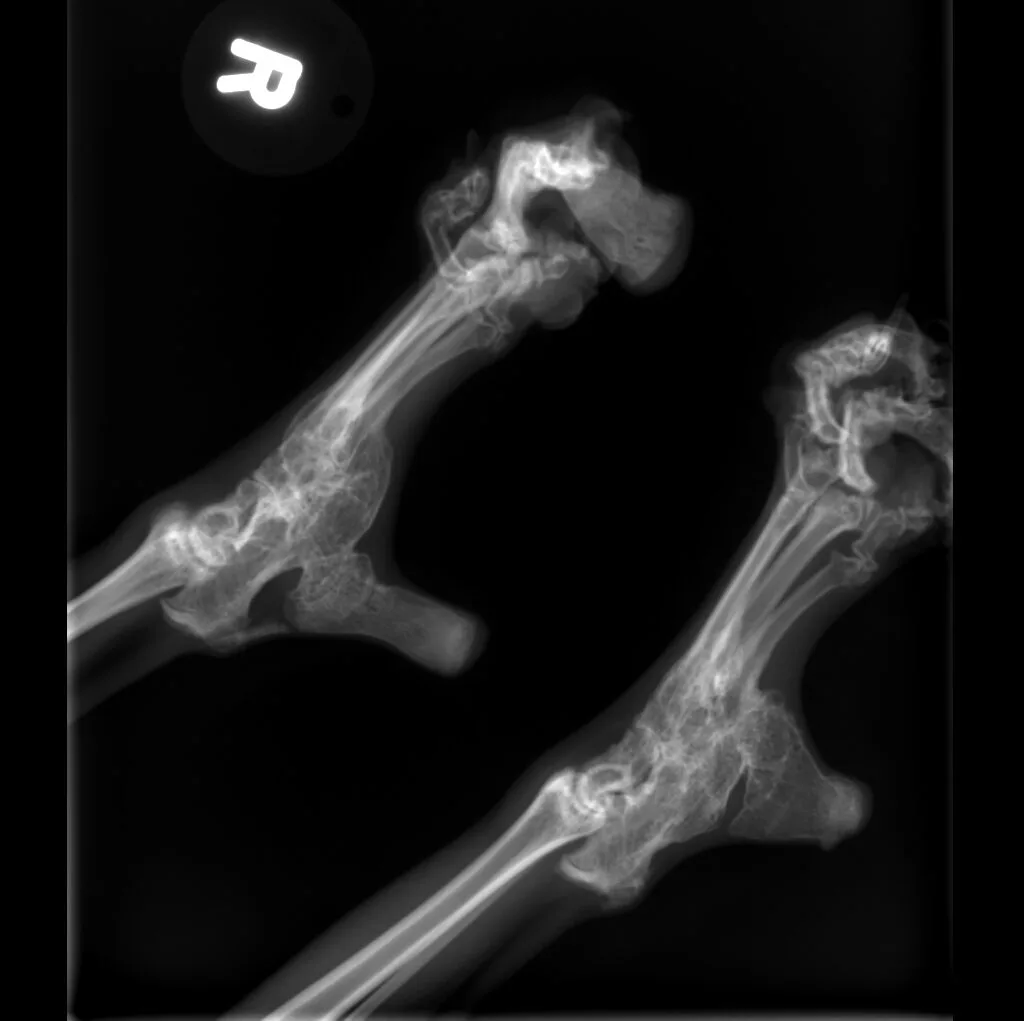

At Grand Ave. Pet Hospital, we utilize digital radiography to diagnose and monitor a wide range of medical conditions in pets. Digital X-rays provide clearer images, faster results, and safer radiation levels, ensuring the best possible care for your furry companion.

Digital radiography offers superior imaging quality and precision compared to traditional X-ray techniques. It allows us to detect hidden health issues early, leading to faster and more effective treatments.

🔹 Lameness & Joint Issues – Identifying fractures, arthritis, and mobility concerns